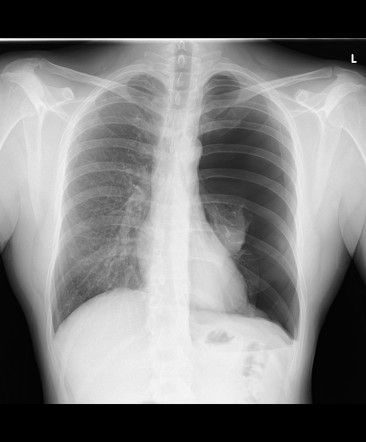

Pneumothorax refers to the abnormal presence of air in the pleural space. The diagnosis is usually clinical based on the status of the patient, However, chest radiograph exhibits characteristic features aiding the diagnosis of pneumothorax. The commonly present features are: - absent lung markings on affected side - radiolucent peripheral space - visible visceral pleural edge - atelectasis may or may not be present - subcutaneous emphysema may or may not be present - shifting of mediastinum Reference: https://radiopaedia.org/articles/pneumothorax Image via: https://radiopaedia.org/articles/pneumothorax